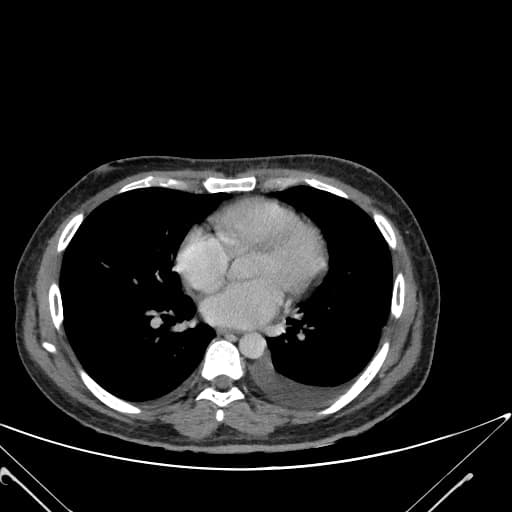

Axial C+ portal venous phase

Đoạn hồi tràng cuối (terminal ileum) xuất hiện hình ảnh bất thường lan tỏa với tình trạng giãn nở, dày thành rõ và tăng quang thành. Không thấy hình ảnh tắc ruột (no evidence of bowel obstruction).

Có nhiều tổn thương bắt thuốc dạng viền (ring-enhancing) với vùng trung tâm giảm tỷ trọng (low attenuation), kích thước tối đa 9,2 cm x 2,5 cm (trên mặt phẳng ngang), nằm ở mạc treo trung tâm và lan xuống hố chậu phải, gợi ý sự hiện diện của nhiều hạch bạch huyết hoại tử. Hạch bẹn hai bên tăng kích thước nhẹ.

Túi thừa (appendix) bị giãn (đo được tối đa 12 mm), nằm trong rãnh cạnh đại tràng phải, đầu mút chạm vào bờ dưới của thùy gan phải. Túi thừa có hình ảnh tách lớp mỡ (fat stranding) và tăng quang thành rõ. Không thấy sỏi túi thừa (appendicolith), cũng không thấy ổ áp xe quanh túi thừa (periappendiceal collection).

Hình ảnh phù hợp với viêm ruột thừa cấp tính (acute appendicitis). Các hạch giảm tỷ trọng gợi ý khả năng bệnh lao trong ổ bụng và vùng chậu.

Trường hợp này cho thấy các hình ảnh gợi ý lao: hồi tràng cuối bất thường và nhiều hạch mạc treo hoại tử. Bệnh nhân sau đó được thực hiện sinh thiết hạch mạc treo qua nội soi ổ bụng, kết quả giải phẫu bệnh học xác nhận lao.

Các phát hiện ở túi thừa nghi ngờ viêm ruột thừa cấp tính. Các hạch hoại tử kết hợp với hồi tràng cuối bất thường làm tăng khả năng mạnh mẽ của bệnh lao.